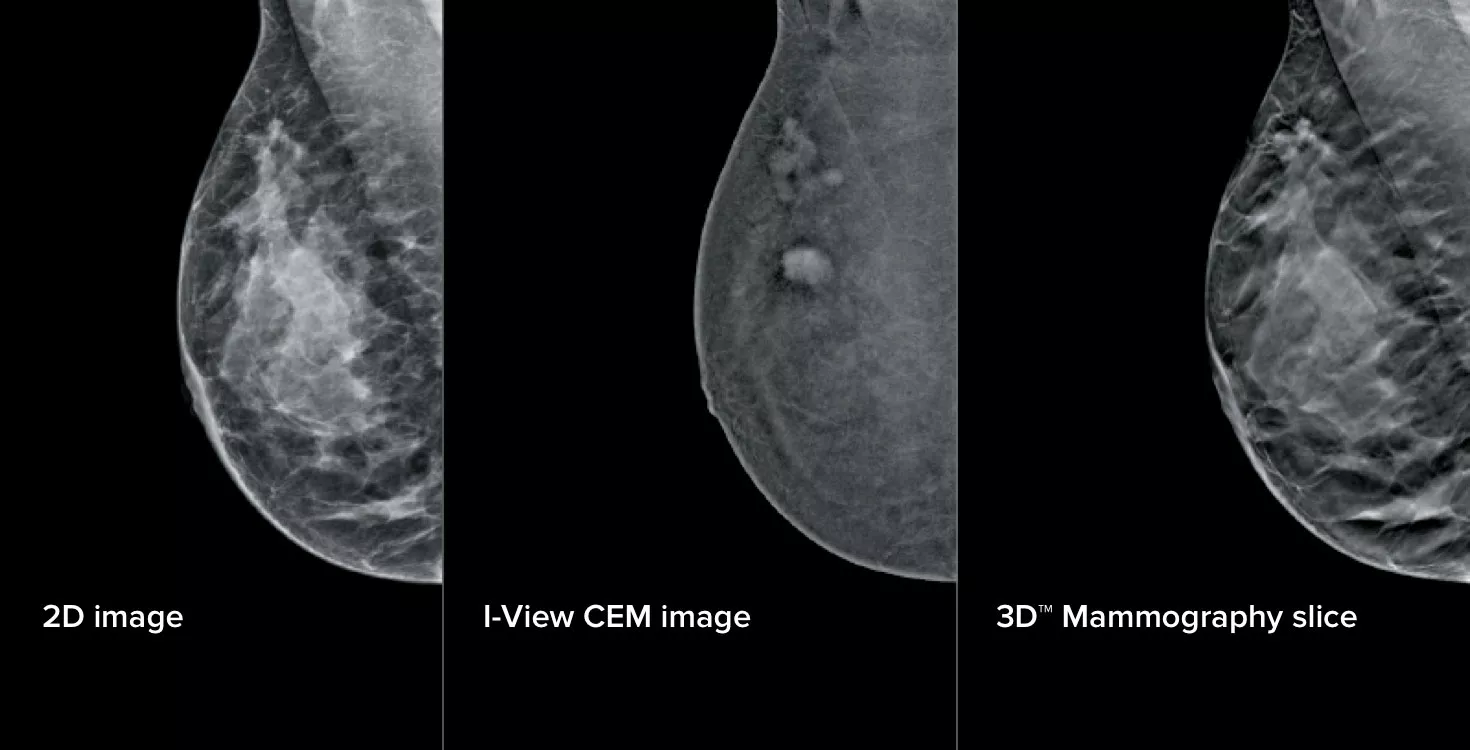

La mammografia con mezzo di contrasto (CEM), la tecnica di imaging che utilizza un contrasto iodato per rivelare le aree con maggiore afflusso di sangue, può aiutare ad evidenziare le lesioni sospette. Il software I-View permette di combinare la potenza della CEM con immagini 2D e di tomosintesi in un'unica compressione, per fornire imaging anatomico e funzionale in un solo esame.1

3 immagini con 1 compressione

Questo software acquisisce informazioni anatomiche e funzionali in un unico esame, sfruttando la capacità di fornire immagini 2D, con contrasto e di tomosintesi in una sola compressione.1